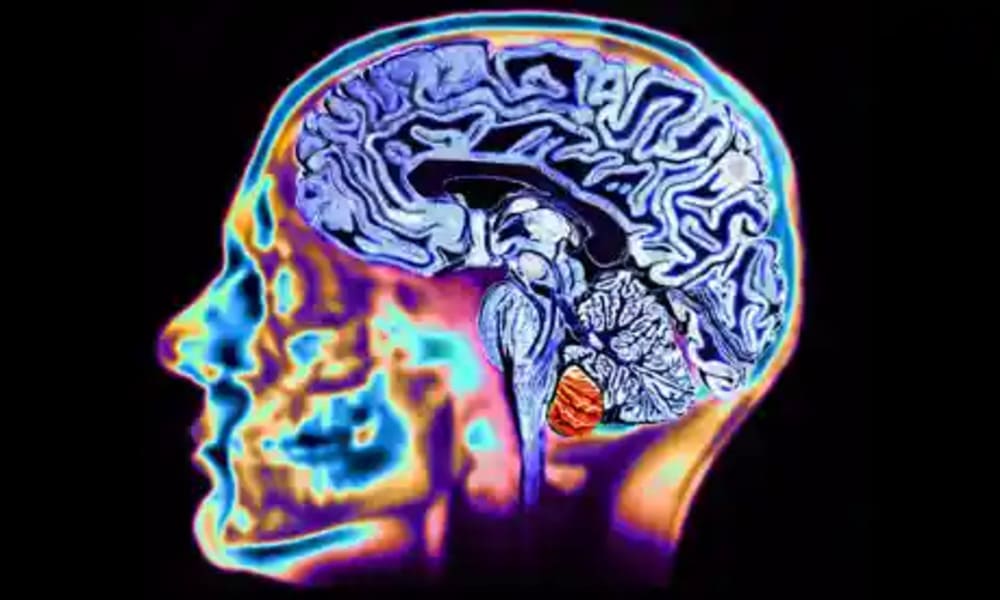

¿Sabías que existen 5 tipos de cerebros? Descubre cuál es el tuyo